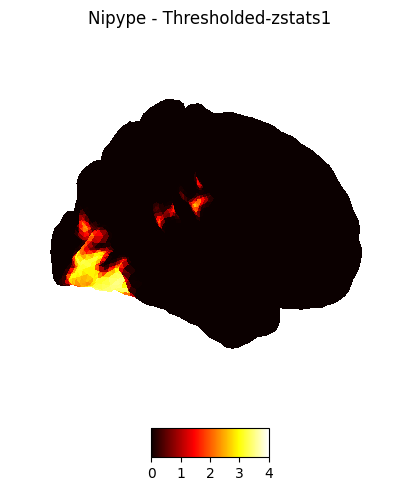

plotting.plot_img_on_surf(nipype_cope2,

views=['lateral'],

hemispheres=['right'],

title="Nipype - Thresholded-zstats2",

cmap = 'hot', colorbar=True)

plotting.show()

plotting.plot_img_on_surf(nipype_cope3,